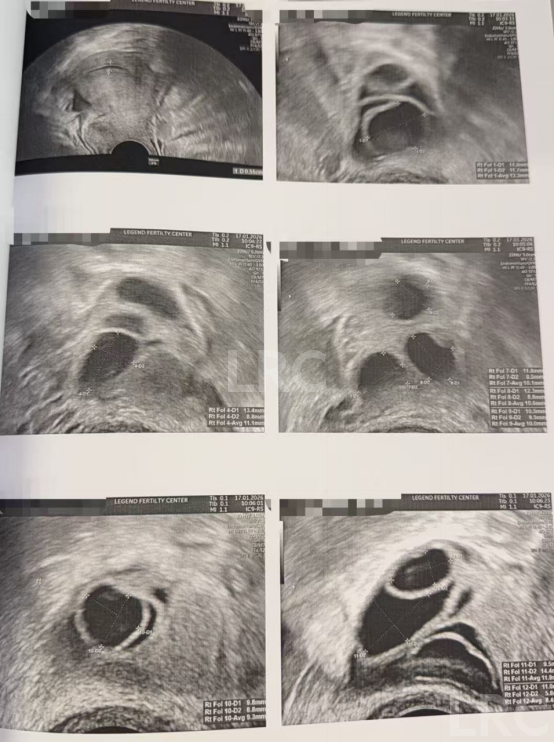

促排第四天

阴超检查(只数能用卵子):

- 右侧卵泡 8 颗 (10,9,9,8,7,7,7mm)

- 左侧卵泡 8 颗 (12,11,10,9,9,9,8,8mm)

促排第六天

阴超检查:

- 右侧卵泡 9 颗 (12,10,9,9,9,8,8,7,7mm)

- 左侧卵泡 9 颗 (13,11,11,11,10,10,9,6,6mm)

促排第九天

- 右侧卵泡 9 颗 (17,17,16,16,15,15,13,12,12mm)

- 左侧卵泡 10 颗 (19,17,16,16,15,15,14,14,13,12mm)

子宫内膜厚度:7.0mm

促排第十天

- 右侧卵泡 9 颗 (20,18,18,18,18,17,17,15,14mm)

- 左侧卵泡 10 颗 (21,20,20,20,20,18,17,13,12,12mm)

子宫内膜厚度:7.9mm